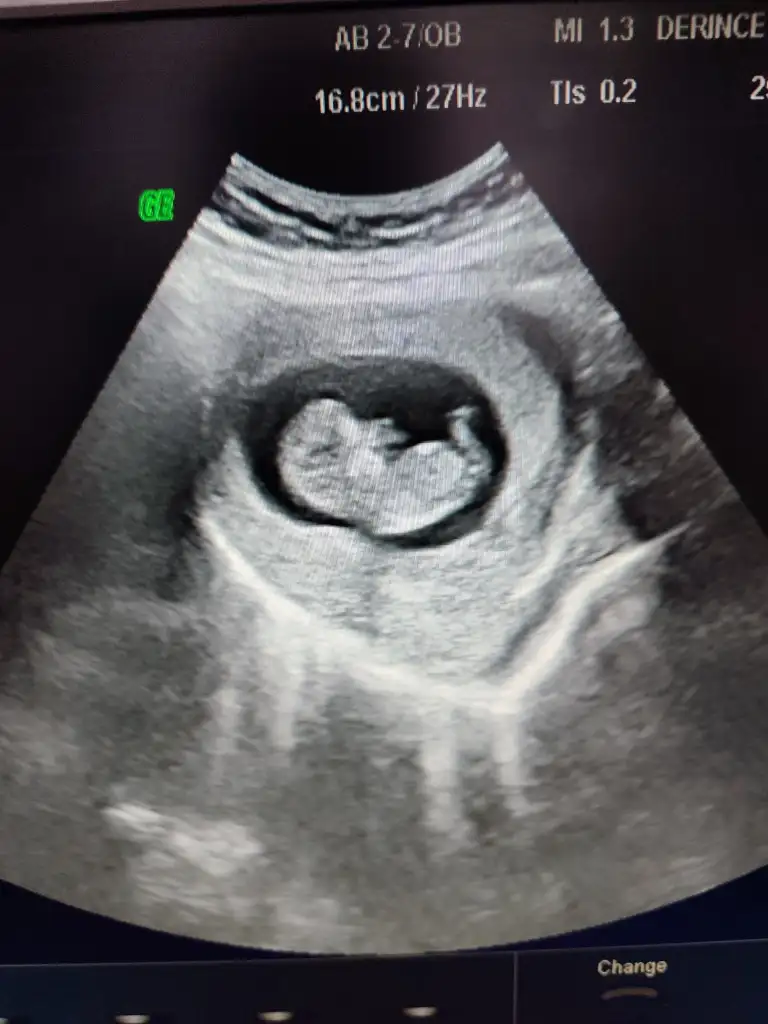

Nub teorisi cinsiyet

Sizce cinsiyeti nedir ? Tahmin alabilir miyim 🤭

Benimkini de yorumlar mısınız 11 haftalık 😊